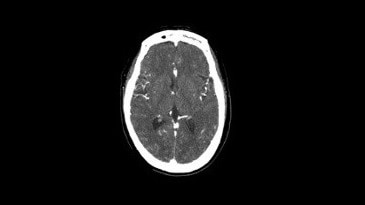

Nöroloji Görüntü Galerisi